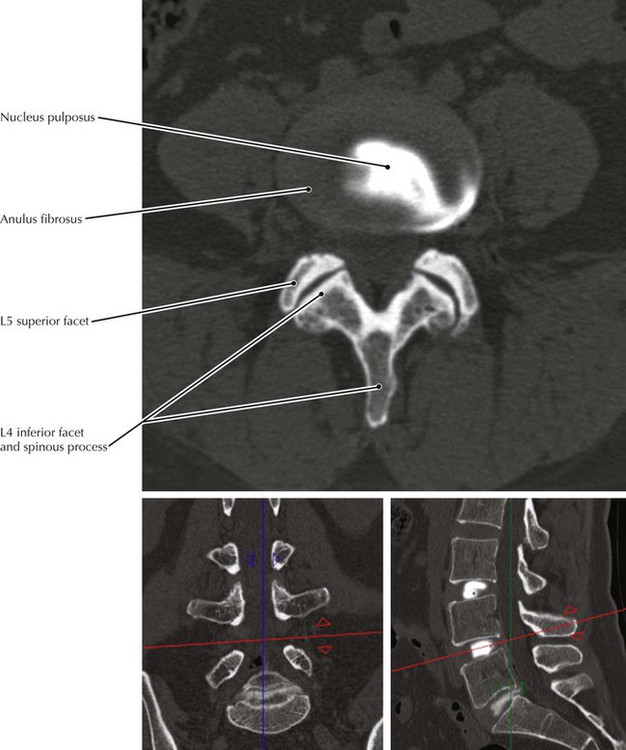

• Contrast material that had been injected into the nucleus pulposus has extravasated through a tear in the anulus fibrosus in this CT scan.

• Note that the main (axial) section shows the spinous process, lamina, and inferior facets of the vertebra above and the superior facets of the segment below.

• The vertebral arch is composed of the two (right and left) pedicles and lamina.

• The parasagittal CT image is at the level of the blue lines in the coronal and axial views. The axial section is at the level indicated by the red line. The coronal reconstruction is at the level of the green line.